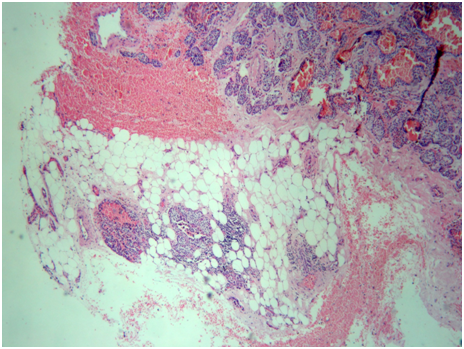

The final histopathology study revealed a 3.5cm x 3.2cm hard nodule adjacent to the left thyroid lobe (Figure 5). The lobe was surrounded by a dense, fibrous capsule that adhered tenaciously to adjacent tissues. Histology showed that chief cells, the predominant cell type, were arranged in solid sheets and organoid groups with a trabecular pattern that infiltrates the capsule and extended to the periparathyroidal adipose tissue with perineural invasion (Figure 6). There was mild atypia cellular without mitotic activity. Scattered foci of comedonecrosis occurred at the periphery of the neoplasm. There were no vascular invasion and no metastatic lymph nodes found. The final diagnosis was a parathyroid carcinoma minimally invasive. No radiotherapy or chemotherapy were administrated. After a period of 44months follow up, not recurrence was detected.

Figure 6 H&E 10x. A thick capsule surrounding the neoplasm, with areas of invasion into the surrounding periparathyroidal adipose tissue.